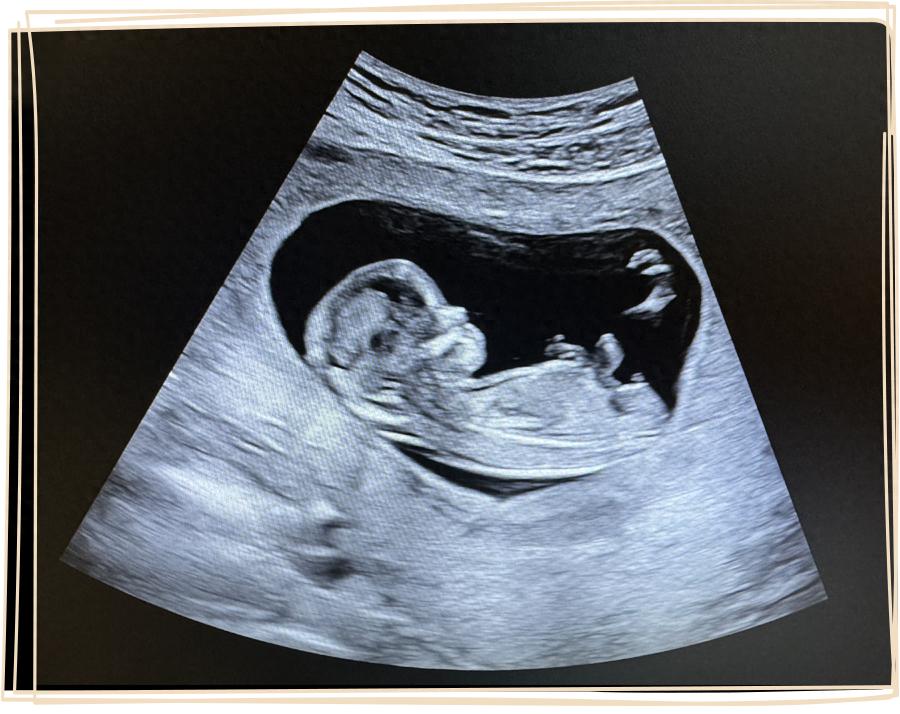

我肚子裏的這個小傢伙,已經 13 周 +,完成了 NT 檢查,在醫院建了卡,是一個結結實實的產科“胎兒”了。

上週做了 NT,已經能清楚看到寶寶的輪廓。期待和 ta 見面,就像我也曾懷抱着同樣的心情,等待年糕和發糕的出生。